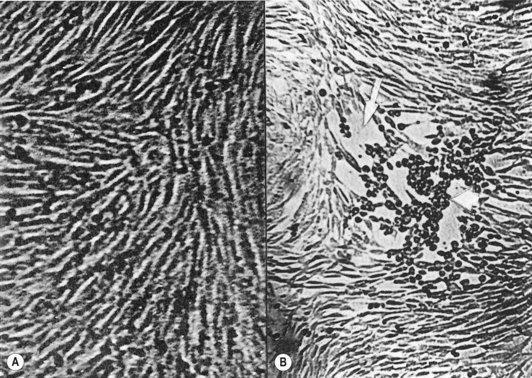

After the inoculation of a monolayer of tissue culture with a clinical sample, it is examined daily for microscopic evidence of viral growth, for about 10 days. Viruses produce different kinds of degenerative changes or cytopathic effects, such as rounding of cells and net or syncytial formation, in susceptible cells (Fig. 6.12). The cell type supporting virus growth and the nature of the cytopathic effect help identification of individual viruses (e.g. herpesviruses growing in monkey kidney cells produce fused cells in which nuclei aggregate to form multinucleate giant cells). The time required for the cytopathic effect to be seen can vary from 24 h up to several days, depending on the virus strain and the concentration of the inoculum. Once the virus is cultured, it can be identified by:

image

Fig. 6.12 Cytopathic effects caused by herpes simplex virus in baby hamster kidney fibroblasts. (A) Confluent monolayer of cells (control); (B) cytopathic effect with rounded cells and areas with detached cells (arrow).